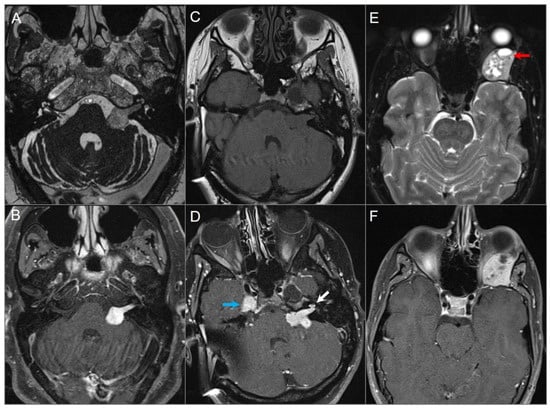

4.4.4. Endolymphatic Sac Tumor